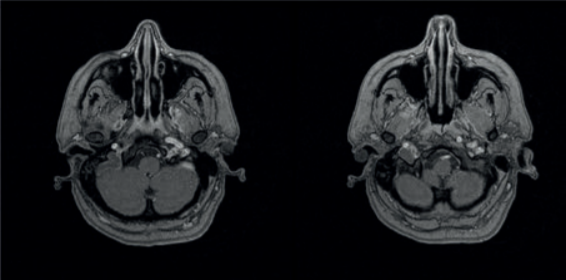

La paciente ingresa en medicina interna, realizándose TAC craneal que es normal; la punción lumbar descartó meningitis. Se realiza RM cerebral (figuras 1 y 2) que muestra el hallazgo de trombosis del seno venoso sagital superior, transverso, sigmoideo y de la vena yugular interna derecha próxima al cráneo, tras administrar contraste v no hay realce sugestivo de infección ni colecciones que sugieran abscesos. Se comienza tratamiento con anticoagulantes con HBPM y dicumarínicos. La cefalea occipital persiste y asocia cervicalgia intensa así como parestesias en miembros superiores de forma aguda y episódica. Es valorada por el servicio de anestesiología precisando de varios bloqueos del nervio occipital mayor bilateral. Tras tres semanas en reposo absoluto, el dolor se controla y la paciente evolucionó satisfactoriamente. Los estudios de imagen posteriores muestran persistencia de trombosis venosa en seno sigmoideo derecho y en la parte más distal del transverso, el resto del transverso y el sagital superior se identifican permeables. Los estudios de perfil trombofílico, autoinmunidad y HLA fueron negativos. Un año después la paciente está estable aunque persisten cefaleas de perfil tensional y migraña episódica que controla con tryptizol. La audiometría mostró recuperación de la pérdida auditiva.

FIGURA 1: AngioRM de cráneo con contraste paramagnético intravenoso en plano axial, trombosis seno sagital superior con el signo del “delta vacío” en plano coronal, transverso derecho, sigmoideo derecho y VYI derecha proximal al cráneo.

FIGURA 2: Secuencia Time Of Flight (2D TPF) coronal, seno transverso-sigmoide derecho de menor calibre que el izquierdo y con trombosis parcial. Seno sagital permeable.